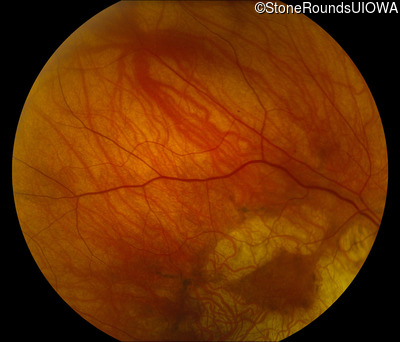

Fundus Photography - Right - 20/32

Exemplar